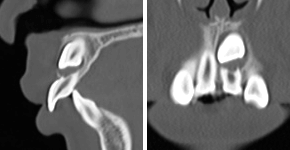

5埋伏歯

主訴:永久歯が出てこない(患者年齢11歳3か月)

診断名:左側上顎埋伏犬歯、左側上顎中切歯歯根吸収

治療に用いた主な装置:リンガルアーチ、マルチブラケット装置

抜歯部位:左側上顎中切歯、左側上顎乳犬歯

治療期間:2年9か月

治療費概算およびリスク副作用:当科で設定している治療費に準じ、リスク副作用についても日本矯正歯科学会Hp掲載内容を説明(上記参照)

初診時

パノラマX線写真

CT画像